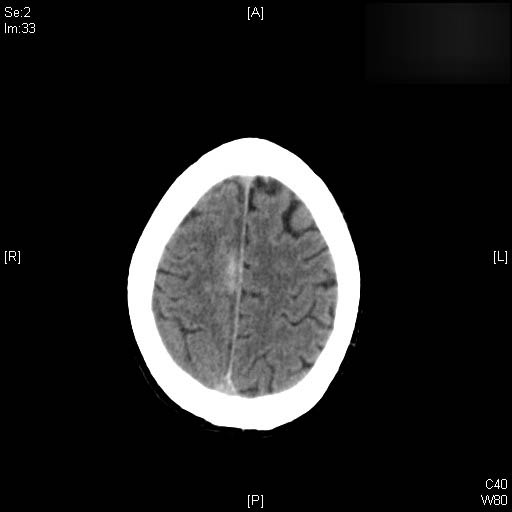

Higroma frontal bilateral